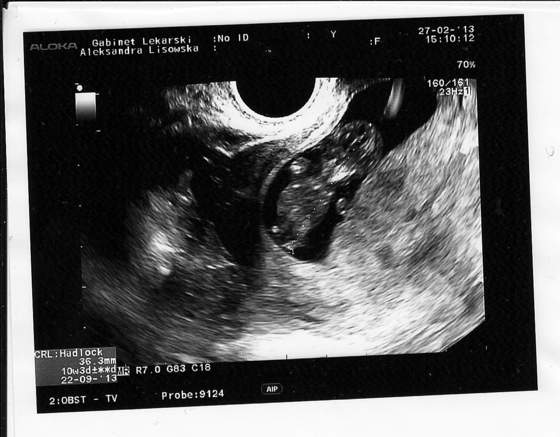

asta aha to zwracam pani doktor honor :-)